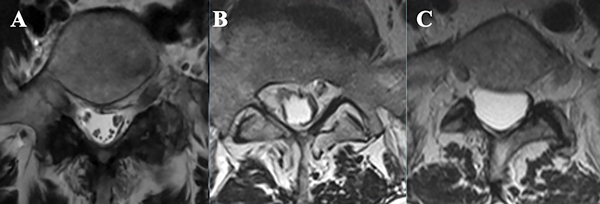

En RMN pueden verse 3 patrones diferentes6,7:

Otros hallazgos en RMN son aglutinación y/o engrosamiento de raíces nerviosas y formación de quistes aracnoidales (Figura 6).

Figura 5: Cortes axiales de RMN en secuencia T2. A- Canal medular de configuración habitual a nivel lumbosacro; B y C- Signo del “saco tecal vacío”: patrón visualizado en RMN caracterizado por adherencia de raíces nerviosas en la periferia de las menínges.

Figura 6: Imágenes de RMN lumbar en secuencia T2, a nivel L2. A- Configuración habitual del canal medular a nivel lumbosacro, se visualizan múltiples raíces nerviosas. A este nivel las raíces de la cola de caballo se ubican en el saco tecal a nivel dorsal, debido al efecto de la gravedad en el decúbito del paciente; B y C- Aglutinación y distribución irregular de raíces nerviosas, hallazgo característico de la aracnoiditis adhesiva; D y E- Imágenes de RMN de la paciente presentada, donde se observa aglutinación y engrosamiento de raíces nerviosas.